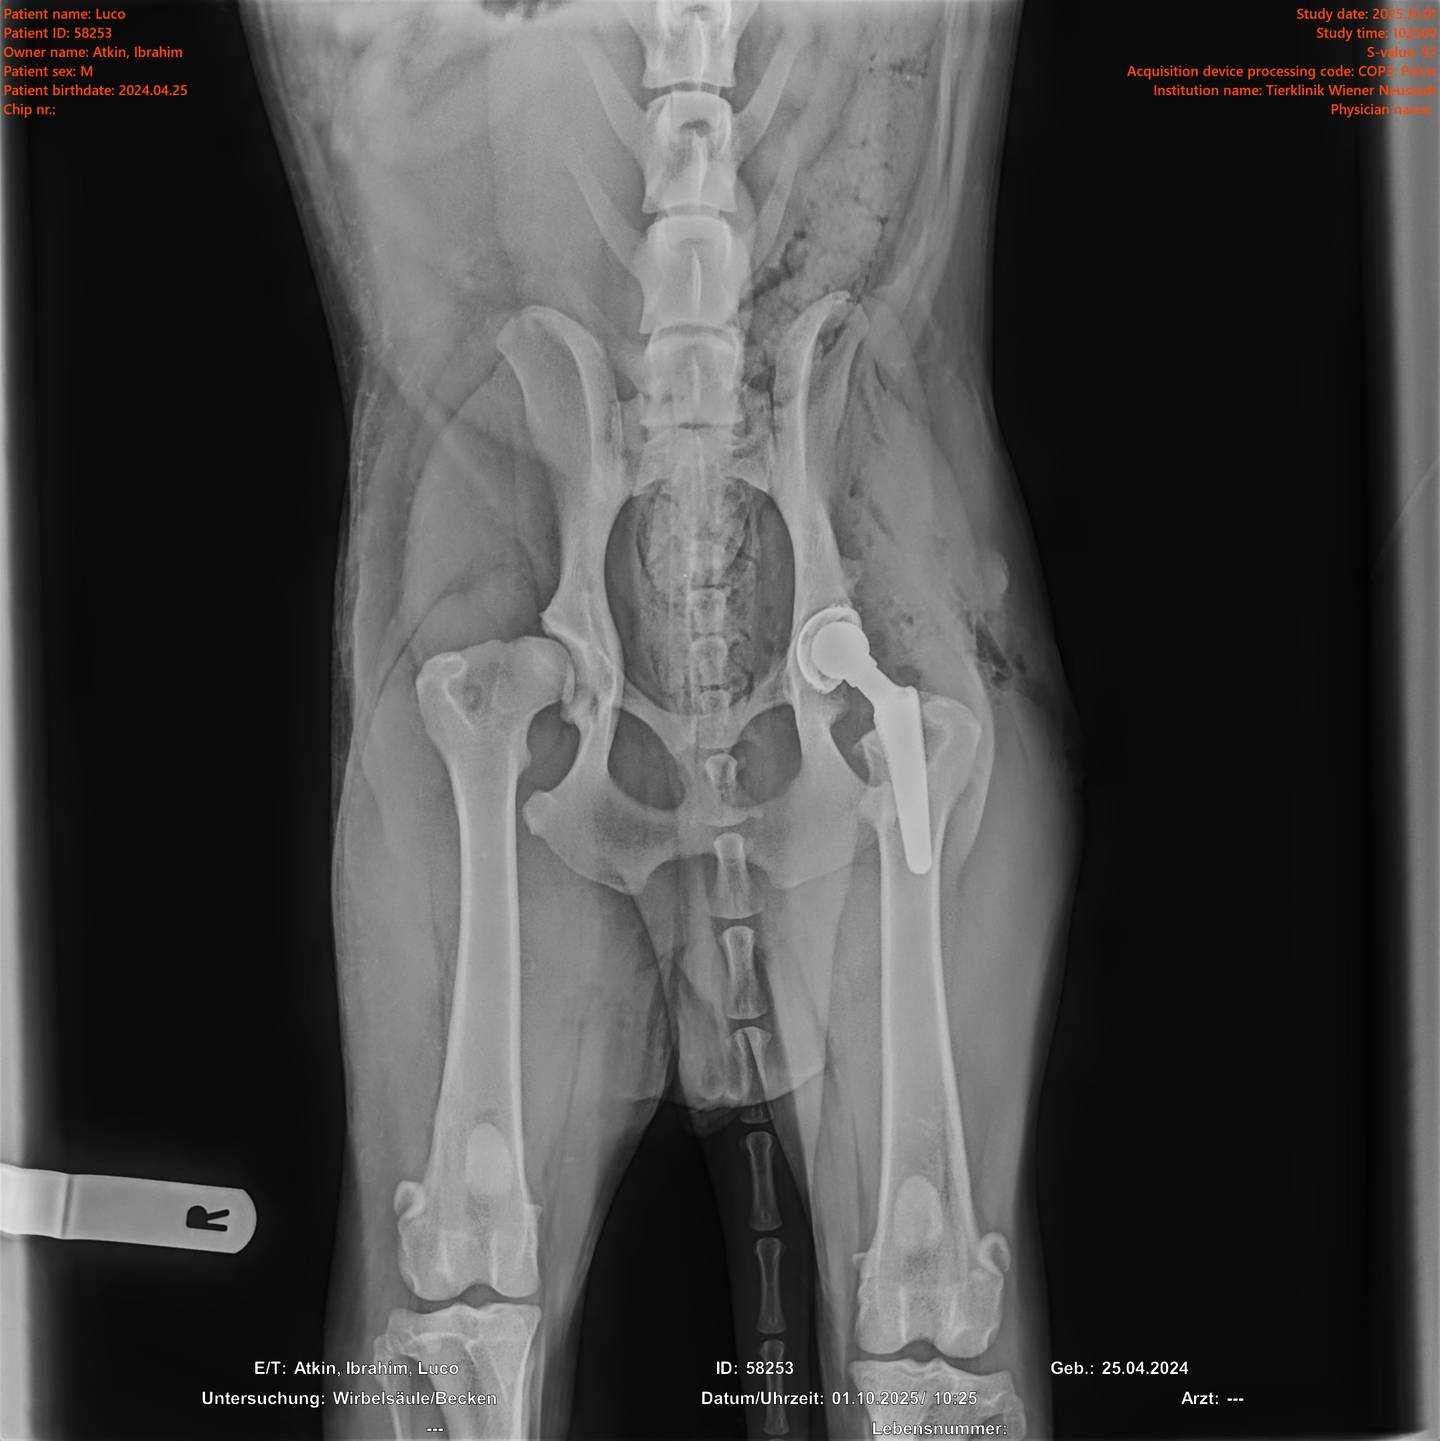

Unser Spezialisten-Team sowie modernste technische Geräte ermöglichen das Angebot eines breiten Spektrums professioneller und komplexer Leistungen. Wir bringen unser medizinisches Wissen in allen Fachbereichen laufend auf den neuesten Stand. Eine strategische Vorgehensweise zur Abklärung der Erkrankung mit dem Ziel, klare Diagnosen zu stellen, hat für uns oberste Priorität. Unsere Tierärzte sind spezialisiert auf Kleintiere und Heimtiere. Zu diesen gehören Hund, Katze, Kaninchen, Meerschweinchen, Frettchen, Hamster, Maus, Ratte und Chinchilla. Wir möchten ausdrücklich darauf hinweisen, dass wir für die Behandlung anderer Tierarten nicht entsprechend ausgestattet sind und daher nicht annehmen. Dazu gehören unter anderem auch Vögel und Exoten.

Tierklinik Wiener Neustadt